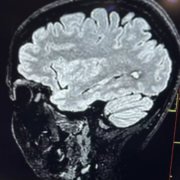

L’organo dell’equilibrio risiede nell’orecchio interno ed è il sistema più complesso esistente nel corpo umano.

Concorrono al mantenimento dell’equilibrio tre sistemi che interagiscono tra loro: il sistema vestibolare, il sistema visivo e il sistema somatosensoriale. Alterazioni o patologie del sistema vestibolare, del sistema visivo e del sistema somatosensoriale, comprendente, in questo ultimo caso, alterazioni dei muscoli, dei tendini, delle ossa, delle articolazioni e della cute, responsabili di squilibri posturali, determinano la sindrome vertiginosa. Molti pazienti dei pazienti arrivati al Centro Siciliano Acufene per vertigini e/o vertigini ed acufene erano soggetti portatori di tatuaggi. Per tale motivo sono stati valutati non solo dal punto di vista vestibolare ma anche posturale per rilevare la variazione dei parametri di elasticità cutanea della zona interessata e le disfunzioni percettive di origine somatoestesica. L’ipotesi al centro dello studio del Csa è che i tatuaggi realizzati soprattutto nella zona del tronco (muscoli posturali), possono creare delle asimmetrie funzionali e quindi essere la causa di alcune disfunzioni.